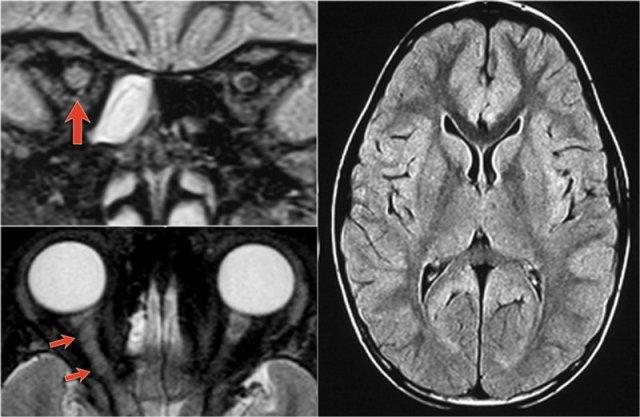

MS: tổn thương khu trú đoạn ngắn hình nêm ở cột sau tủy sống kèm theo các tổn thương chất trắng quanh não thất điển hình.

MRI não cho thấy các tổn thương quanh não thất và một tổn thương ở thể chai.

Các vị trí này rất đặc trưng cho MS.

Ở một bệnh nhân khác có các tổn thương không đặc hiệu trong tủy sống.

Chỉ dựa vào khảo sát cột sống đơn thuần, chúng ta có một chẩn đoán phân biệt rộng.

Tuy nhiên khi khảo sát thêm não, sẽ rõ ràng rằng chúng ta đang đối mặt với MS.

Tiếp tục xem các hình ảnh của não.

Trong trường hợp này, các hình ảnh trên não rất hữu ích.

Vị trí của các tổn thương rất điển hình: cầu não, quanh não thất và dưới vỏ não.